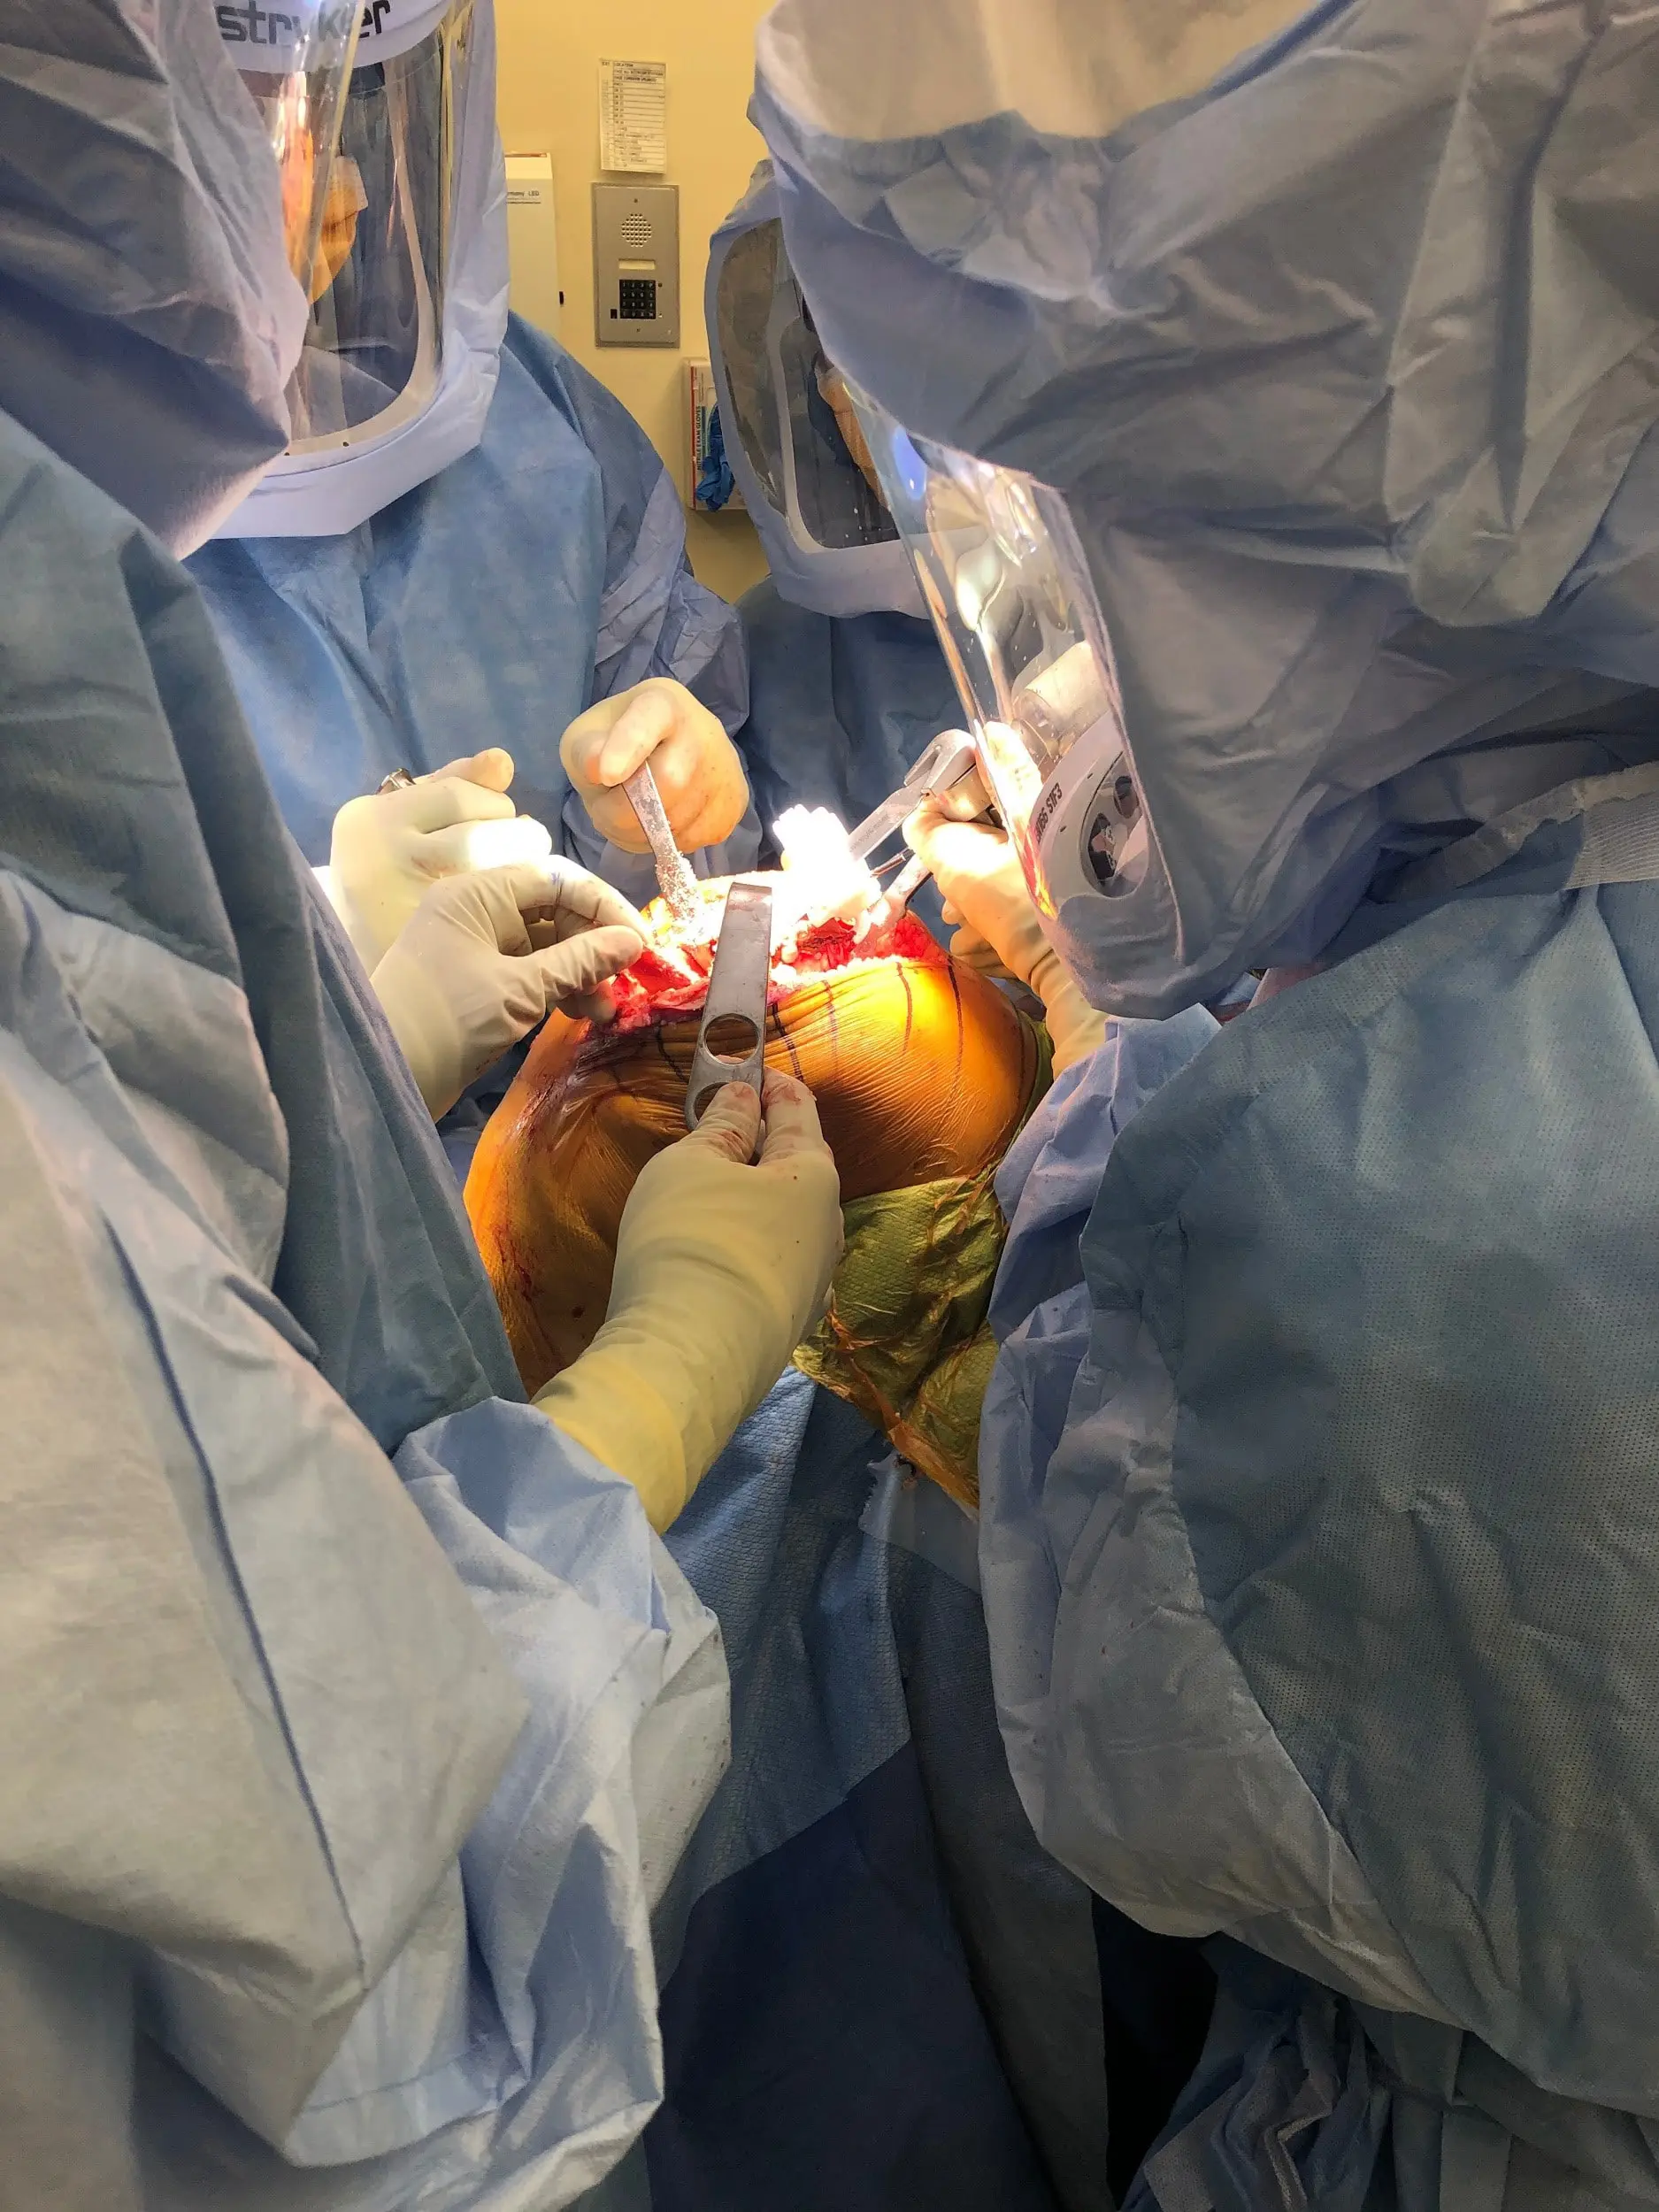

Operative report:

Anesthesia was obtained by the anesthesiologist. The patient was then definitively positioned and the tourniquet was used to exsanguinate the extremities. A straight incision was used for the arthrotomy. Skin and subcutaneous tissues were incised. Medial parapatellar arthrotomy was then performed. The tibial cutting guide was used to make the tibial cut and the tibia was then prepared.

Attention was then turned on towards the femur. The femoral cutting guides were used for preparing the femur and then medially and laterally, laminar spreaders were then used and the remainder of the cruciates and the meniscus were then debrided. Gap balancing was performed and found to be perfect.

The patella was resected. Drill holes were made in the patella. The trial patella was placed into position followed by a trial of the femur, trial tibia, and the polyethylene was then placed over the tibia.

The knee was reduced and trialed through a full physiological range of motion and excellent stability and excellent patella tracking was then observed. The trial components were then removed.

The injection was given. A thorough lavage was given. The femur was cemented into position. Excess cement was removed. The tibia was cemented into position. Excess cement was removed.

Poly was then placed over the tibia and the knee was reduced and held in full extension with a bump under the ankle. Patella was then cemented into position and held with a patellar clamp.Medial patellar arthrotomy was closed with Vicryl and Stratafix. The wound was closed in layers. Sterile dressing was then applied over the wound. The tourniquet was then let down, and the patient was transferred to the postoperative care unit in stable condition.